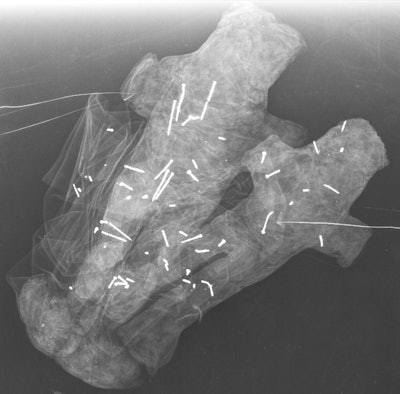

Three dolls made of red fabric.Finally, the paired dolls were not clearly identifiable as male or female, they wrote. The fact that they are a duo could signify a couple, a father and son, or siblings. The researchers found 58 needles in these two dolls: 20 in the white doll, 33 in the black doll, and five scattered across the fabric of each.

Doll pair made of black and white fabric.Cracking the code